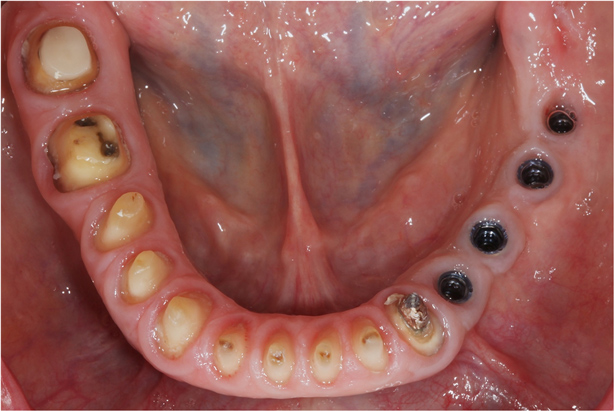

This patient previously presented with esthetic concerns but was reluctant to proceed with reconstructive dental treatment (Figure 19 and Figure 20). She had been monitored for several years and advised of the benefits of an interdisciplinary treatment plan including periodontal, dental implant, and prosthodontic therapy. The diagnosis included occlusal trauma, loss of vertical dimension, lack of posterior tooth support, and supra-eruption. There was also gingival asymmetry, lack of attached gingiva, lateral ridge defect for the mandibular left molar region, pneumatization of the maxillary right sinus, and alloy tattoo of the gingiva for the maxillary right bicuspids. Eventually the mandibular left second bicuspid, which was an abutment for a fixed partial denture, fractured, resulting in an abscess and significant bone loss localized to this abutment tooth (Figure 21). At this point, given the need for extraction and now more limited posterior chewing capability, the patient requested a comprehensive consultation and treatment plan for the reconstructive therapy she had previously elected to postpone.

Figure 19 This patient presented with esthetic and functional concerns, but was reluctant to proceed with reconstructive dental treatment.

Figure 19

Figure 20 Intraoral examination revealed multiple concerns, including loss of vertical dimension, lack of posterior tooth support, and supra-eruption. There was also gingival asymmetry, and minimal zones of attached gingiva.

Figure 20